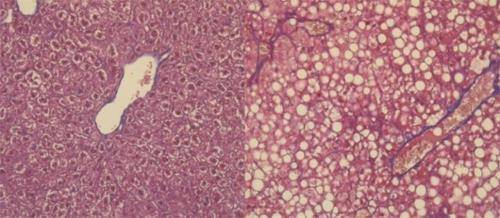

![지방이 쌓인 간(우측) [스위스 제네바의대 제공 / 재판매 및 DB 금지]](https://img3.daumcdn.net/thumb/R658x0.q70/?fname=https://t1.daumcdn.net/news/202006/06/yonhap/20200606110256964ehpe.jpg)